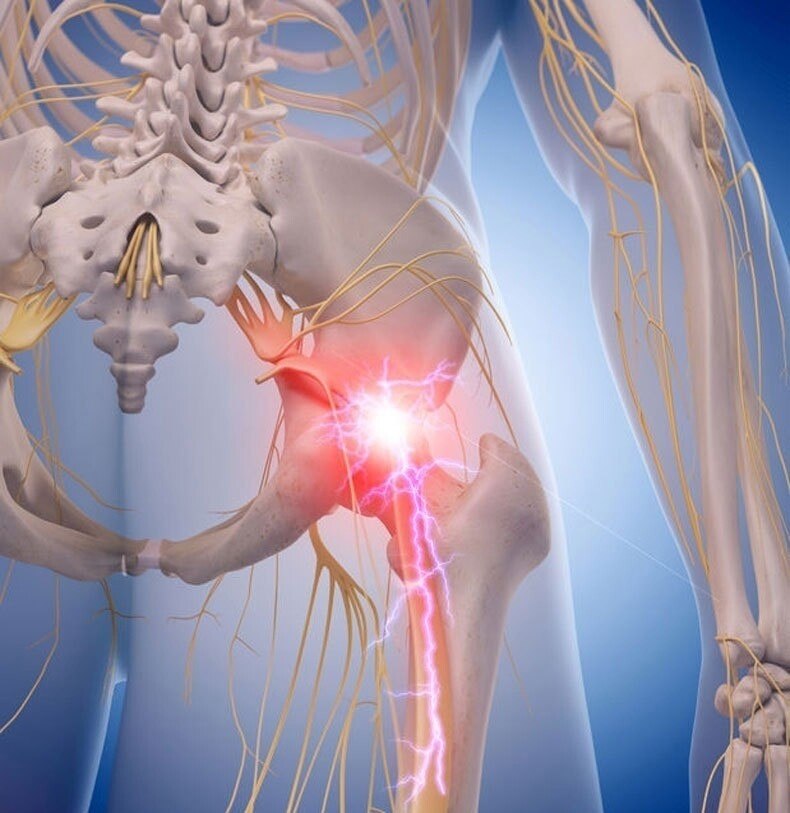

Облегчаем боль при защемлении седалищного нерва

Применение компрессов быстро снимает боль при защемлении седалищного нерва. Их действие обусловлено тем, что они расслабляют мускулатуру в пораженной зоне.

Что такое седалищный нерв?

Этот нерв является самым толстым и длинным в человеческом теле. Он начинается в спинном мозге, проходит через поясничный отдел и доходит до нижних частей ног. Седалищный нерв обеспечивает чувствительность и подвижность в: бедрах, коленях, икрах, щиколотках, стопах и пальцах ног

В целом защемление седалищного нерва вызывает следующие симптомы:

жжение

покалывание

пульсирующая боль

потеря чувствительности

слабость в ногах и ступнях

Кроме того, слабость ощущается во всей нижней части тела.

Самой распространенной причиной этого синдрома являются повреждения костей, которые формируют канал для седалищного нерва. Также травмирование нерва может произойти вследствие наличия опухоли, например, хондросаркомы. Она сдавливает нерв, что вызывает сильную боль. Другой ее причиной может быть беременность. Увеличившаяся матка давит на внутренние органы, а те, в свою очередь, на мышцы таза.

Применение компрессов быстро снимает боль при защемлении седалищного нерва. Их действие обусловлено тем, что они расслабляют мускулатуру в пораженной зоне.

Что такое седалищный нерв?

Этот нерв является самым толстым и длинным в человеческом теле. Он начинается в спинном мозге, проходит через поясничный отдел и доходит до нижних частей ног. Седалищный нерв обеспечивает чувствительность и подвижность в: бедрах, коленях, икрах, щиколотках, стопах и пальцах ног

В целом защемление седалищного нерва вызывает следующие симптомы:

жжение

покалывание

пульсирующая боль

потеря чувствительности

слабость в ногах и ступнях

Кроме того, слабость ощущается во всей нижней части тела.

Самой распространенной причиной этого синдрома являются повреждения костей, которые формируют канал для седалищного нерва. Также травмирование нерва может произойти вследствие наличия опухоли, например, хондросаркомы. Она сдавливает нерв, что вызывает сильную боль. Другой ее причиной может быть беременность. Увеличившаяся матка давит на внутренние органы, а те, в свою очередь, на мышцы таза.